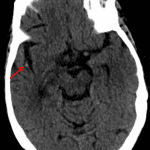

- Focal hyperdensity associated with an M2 branch of the right MCA

- Acute right MCA territory infarct (dense vessel sign)

Focal hyperdensity associated with an M2 branch of the right MCA concerning for age-indeterminate thrombus. Consider CTA for further evaluation. No definite CT findings of infarct; however, MRI is more sensitive for acute ischemia.